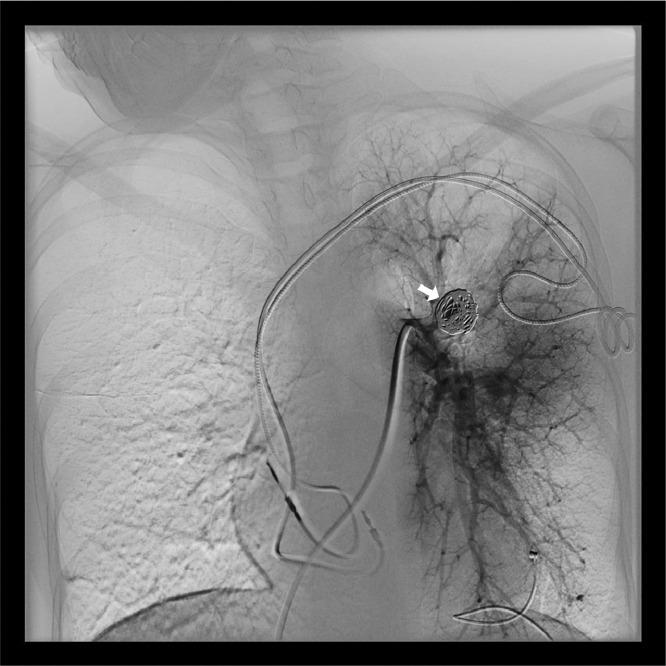

A peripheral pulmonary artery aneurysm (PAA) is a dilatation involving all 3-vessel wall layers (the intima, media, and adventitia) of a distal pulmonary artery. It represents a rare but potentially life-threatening condition. There are only some reviews of transcatheter embolization of unruptured idiopathic peripheral PAAs. Association with cardiac diseases, infections, vascular anomalies, pulmonary hypertension, and vasculitis has been noted. We report a case of a 38-year-old woman, with a history of third-degree atrioventricular (AV) block, treated with pacemaker placement, who presented a PAA in the left pulmonary lobe. Transcatheter coil embolization was performed, using a triple coaxial catheter system (a 6F outer, a 5F intermediate, and a 2.4F inner catheter) to prevent rupture and the aneurysm was successfully embolized. Although there is no consensus on the treatment for unruptured idiopathic peripheral PAAs, transcatheter embolization may be a promising treatment option.